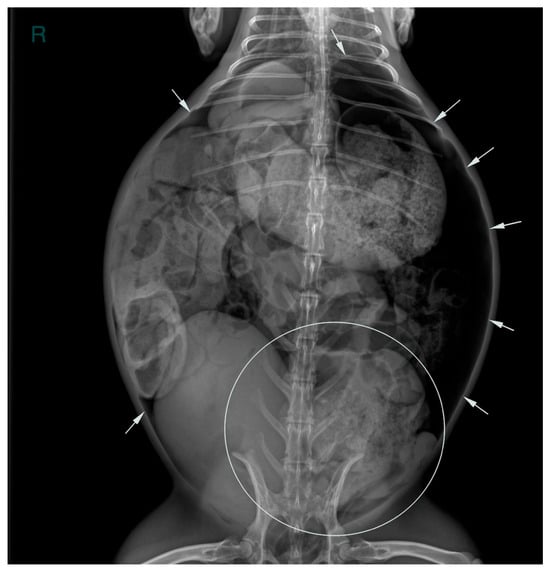

2. Case Description